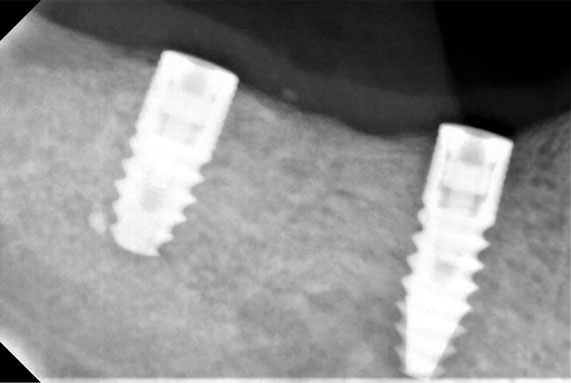

Η απώλεια ενός ή περισσοτέρων δοντιών αποκαθίσταται πλέον με εμφυτεύματα.΄Ολοι λίγο ή πολύ γνωρίζουν πια γι΄αυτά ,αλλά το πόσο εύκολη και προσιτή είναι η τοποθέτηση τους είναι μία απορία πολλών.Κι όμως η διαδικασία τοποθέτησης τους και τα ποσοστά επιτυχίας τους ,σε συνδιασμό με αισθητή μείωση των τιμών τους τα έχουν κατατάξει στις καθημερινές οδοντιατρικές πράξεις.Στο οδοντιατρείο μας τα εμφυτεύματα γίνονται μετά από προσεκτική μελέτη του κάθε περιστατικού ξεχωριστά και με την συνεργασία εξαίρετου συνεργάτη Γναθοχειρουργού.